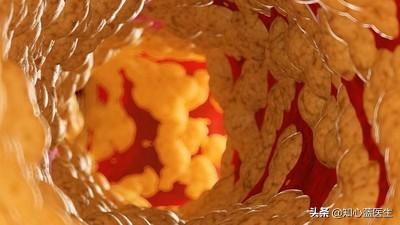

冠状動脈は心臓に血液を供給する主な動脈で、年齢、三高、慢性病、悪習慣などの影響を受けて、心臓に血液を供給する冠状動脈も他の動脈と同じように、アテローム性動脈硬化症、狭窄、プラークなどの問題が現れる、冠状動脈の狭窄が50%以上の場合、通常、心臓の血液供給と酸素供給が大きな影響を受けると考えられ、このような場合、冠状動脈性心臓病と診断することができます。このような場合、冠動脈性心疾患と診断することができる。

最初の状況は急性心筋梗塞である。冠動脈の動脈硬化が進行し続けると、冠動脈に脂質が沈着して形成されたプラークが徐々に変化し、一部の不安定なプラークが特定の要因の影響を受けてプラークの破裂が起こると、血液中の凝固物質が凝集して血栓が形成され、冠動脈の血管が閉塞し、心臓の血液供給に深刻な影響を及ぼし、重篤で緩和困難な狭心症、胸部圧迫感、心筋梗塞に関連する症状を引き起こす可能性があります。心筋梗塞に関連する症状として、死が近いという感覚などがある。

(2) 動脈硬化:冠動脈性心疾患とは、血液中の脂質成分が内皮細胞の下に侵入し、炎症反応が起こり、動脈硬化性プラークが形成されることによって引き起こされる病気のことである。

- 冠動脈は、心臓そのものに血液を供給する動脈であり、動脈硬化、または私たちがよく呼ぶプラークである。冠動脈はプラークを生成し、プラークは徐々に大きくなり、心臓への血液と酸素が不足し、さまざまな症状を引き起こす。

一般に、冠動脈を塞いでいるプラークが50%以下であれば、冠動脈性心臓病とは呼ばず、冠動脈硬化症と呼び、現時点では比較的軽症であるが、将来的にはより危険である。

- プラーク表面の潰瘍やプラーク破裂などのプラークの不安定性は血小板凝集を引き起こし、血管の狭窄を増大させる。

冠動脈性心疾患とは、冠動脈アテローム性動脈硬化性心疾患の略称であり、主に心臓に血液を供給する動脈である冠動脈のアテローム性動脈硬化によって引き起こされる。動脈にアテローム性動脈硬化症が起こると、動脈の内表面にプラークが形成され、プラークが蓄積するほど動脈の直径が狭くなる。狭窄の程度が50%未満であれば、心筋への血液供給には影響しないので、一般的に症状はありませんが、50%以上になると、心筋への血液供給に影響を及ぼし、心筋の酸素消費量が増加しても、心筋が十分な酸素を得ることができず、心筋虚血、低酸素状態になると、胸部圧迫感、胸痛の症状が誘発され、これを狭心症と呼びますが、狭心症の症状は活動を停止すると徐々に緩和されます。狭窄の程度がさらに悪化したり、局所的なプラークの破裂、冠動脈の血栓閉塞によって心筋虚血が生じたりすると、狭心症の程度はさらに悪化し、緩和されない状態が続き、閉塞が解除されなければ心筋虚血壊死を引き起こし、ついには患者の突然死に至ることもあり、これが心筋梗塞と呼ばれるものです!